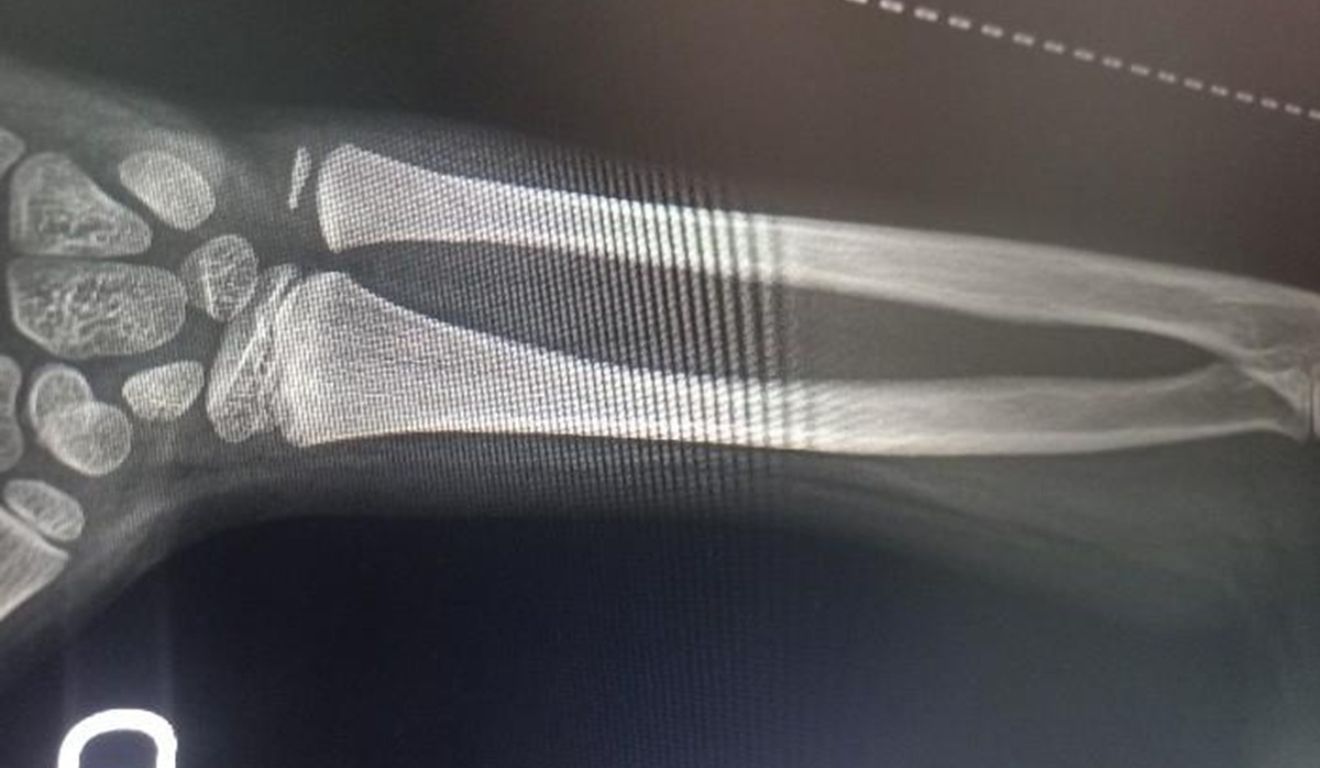

Por isso, a escola seguiu o protocolo do Conselho Tutelar e acionou o órgão de proteção à criança. Além disso, os docentes levaram o garoto ao Hospital Pequeno Anjo, onde a fratura foi confirmada. Ele precisou ser engessado.